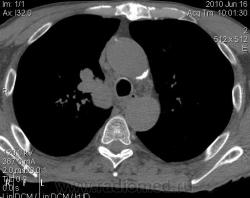

Мужчина 69 лет, с последствием ОНМК находился в доме-интернате для инвалидов. В анамнезе пневмония справа и исходом в пневмосклероз. ФЛГ не проходил 1.5 года. Анализы: СОЭ 20 мм/ч, остальное - без особенностей. Поступил в неврологическое отделение с диагнозом: повторное ОНМК. Невролог заподозрил метастазы головного мозга, направил на рентгенографию легких. После выявленых изменений в правом легком, пациент направлен на КТ головного мозга и грудной полости. От контрастирования и бронхоскопии категорически отказался.

По поводу подозрения на туберкулез пациента в прошлом нодократно проверяли, исключили. ФЛГ архива у меня нет. Все только со слов пациента. Кальцинаты в корне массивные. Трудно сказать, откуда опухоль (если это не конгломерат лимфоузлов!) плотностью 35 ед.Н - то ли из вехнедолевого бронха, который имеет культю 0.4 см и заканчивается выпуклым контуром, но при этом сохраняется воздушность почти всей доли; то ли периферический с центром в прикорневой зоне и вторичным прорастанием ВДБ. К сожалению забыла про снимок легких, на днях выставлю. Я первоначально считала периферический (верхушка, на фоне пневмосклероза) с мтс средостения. По плотности на верхушке узелок 5 ед.Н, только поэтому засомневалась, где же первичный. Лимфоузлы средостения множественные, до 2 см. Кроме того, на верхней стенке правого главного бронха есть мелкое образование такой же 35 е.Н плотности, то ли аденома, то ли прорастает... Без бронхоскопии - только гадать

это периферический рак S2 в/доли правого легкого с мтс во внутригрудные л/узлы.

А тут нечего гадать - данную демонстрацию можно поместить в учебник: узловое образование, с бугристыми, лучистыми контурами, связаное с плеврой, "дорожкой" к корню, перифокальной инфильтрацией. Корень расширен полицикличен за счет конгломерата увеличеных бронхопульмональных, трахеобронхиальных и бифуркационных л/узлов, значительно сдавливающих в/долевой бронх, с нарушением вентиляции в/доли.

Центральный рак ВДБ справа с мтс в л/узлы паратрахеальные нижние, верхние справа, БФ. МТС в головной мозг. А про печень мало сканов

Мне кажется в 6 сегменте печени мтс + еще мтс поражение левого надпочечника вероятнее всего. Мтс в нижние паратрахеальные (с обеих сторон)+бифуркационные л/у. Поражения верхних паратрахеальных не вижу (на коронарах), аксиалы - не показыны сканы выше верхнего края дуги аорты, так что я бы не говорил про поражение верхних медиастинальных лимфоузлов (хотя тут это уже не принципиально) + мтс в головной мозг. А так - центральный рак правого легкого.